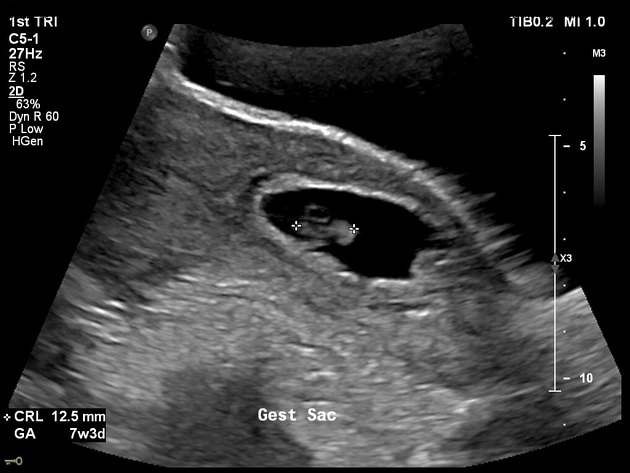

• Thai quý I

• VI. Thai ngoài tử cung

• Thai ngoài tử cung đoạn vòi (Tubal ectopic pregnancy)